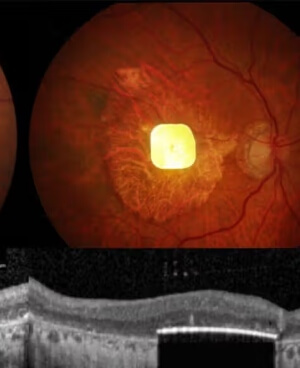

Innovación médica permite actuar ante derrames cerebrales antes del hospital